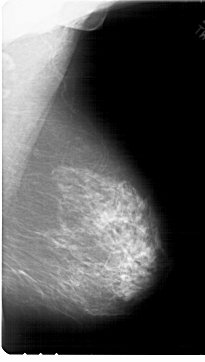

A_1789_1.RIGHT_CC

RIGHT_CC LINES 6421 PIXELS_PER_LINE 3811 BITS_PER_PIXEL 12 RESOLUTION 43.5 NON_OVERLAY